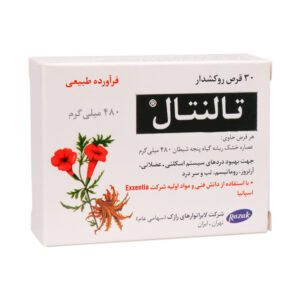

بهترین قرص های غضروف ساز کدام اند؟

محصولات متعددی در بازار جهت بهبود روند ترمیم و بازسازی غضروف وجود دارند که در اینجا به چند مورد از این موارد خواهیم پرداخت: